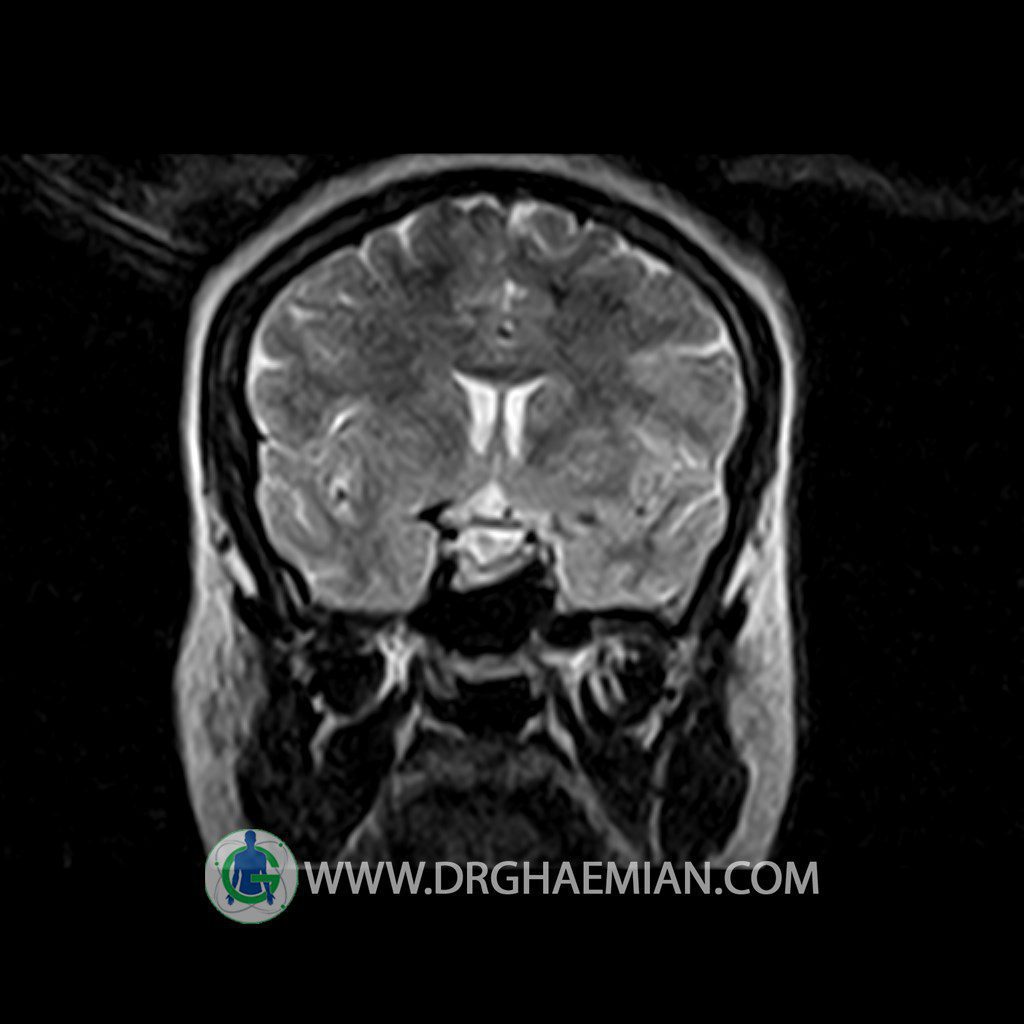

ام آر آی هیپوفیز یک روش تصویر برداری است که از غده هیپوفیز (غده ایی کوچک در مغز که هرومون ها و دیگر غدد بدن را کنترل می کند) و ناحیه های پیرامونش در مغز تصاویری ایجاد می کند. در این کیس سلای نسبتا خالی در ناحیه هیپوفیز بیمار مشاهده می شود.

– Extension of suprasella cistern to sella with thin pituitary gland in floor of sella ( partial empty sella )

is seen